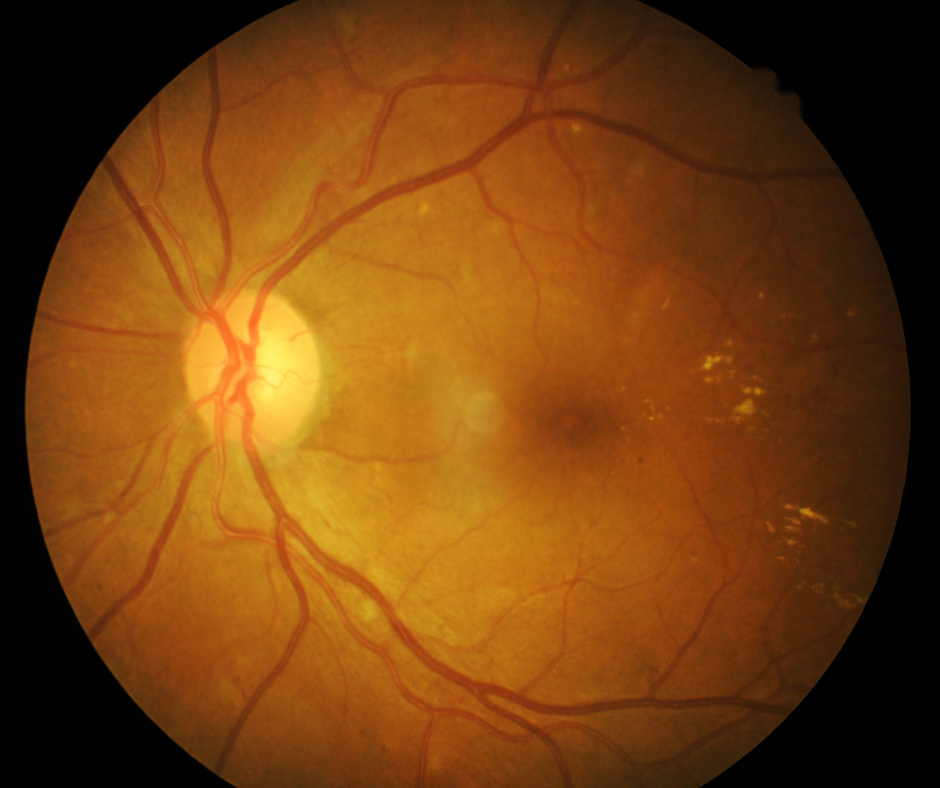

Diabetisches Makulaödem

Die diabetische Retinopathie (eine Netzhautveränderung) ist eine häufige Begleiterscheinung bei Diabetes mellitus. Das diabetische Makulaödem ist eine Verdickung der Netzhaut an der Stelle des schärfsten Sehens und ist die häufigste Ursache für den Sehverlust.

Altersbedingte Makuladegeneration (AMD)

Die altersbedingte Makuladegeneration – kurz AMD – ist eine chronisch verlaufende Netzhauterkrankung, die meist ab dem 55. Lebensjahr auftreten kann.